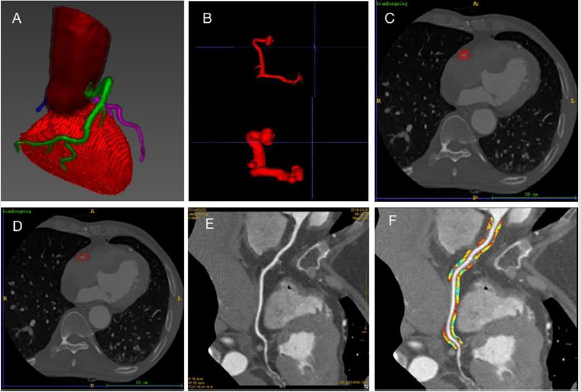

A CQK software (Coronary Artery Quantitative Analysis Kit, GE Healthcare, China) dedicated to coronary analysis was used to extract the PCAT region (Figure1). Firstly, the coronary CTA DICOM images were imported into CQK software, then, the RCA was segmented using a pretrained V-NET model, the RCA was expanded using the size same to the vessel diameters. The expanded vessels extracted the initial vessels to obtain the pericoronary regions. Finally, -190 HU to -30HU were adopted as adipose CT decaying range to filter the non-adipose voxels to get the ROI of PVAT. Pyradiomics software (version 3.0.1, https://pyradiomics. readthedocs.io/en/latest/) was used to extract the radiomic features of PCAT using example CT.yaml setting files. Pyradiomics is a widely accepted feature extraction tools complied to the ISBI. 1218 features including shape features, first-order features and texture features were extracted. Shape features describe the geometry of the ROI, first-order represent the gray value distribution within the ROI. Texture features reflect the gray value distribution in space.

Figure 1: Flowchart of PCAT feature extraction.

A. 3D representation of Coronary artery segmentation.

B. RCA expanded using the size of the maximum diameter of the vessel (figure above, original RCA; figure below, expanded RCA).

C. The peri-coronary area obtained.

D. PCAT obtained after -190 ~ -30HU filtration;

E. Surface reconstruction of artery;

F. Adipose tissue extracted around RCA. RCA: right coronary artery. PCAT: peri-coronary adipose tissue.